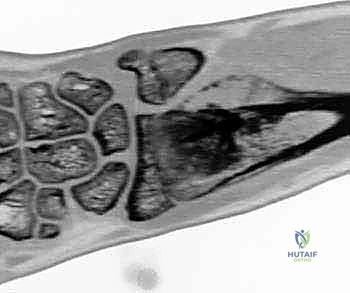

Clinical & Radiographic Imaging